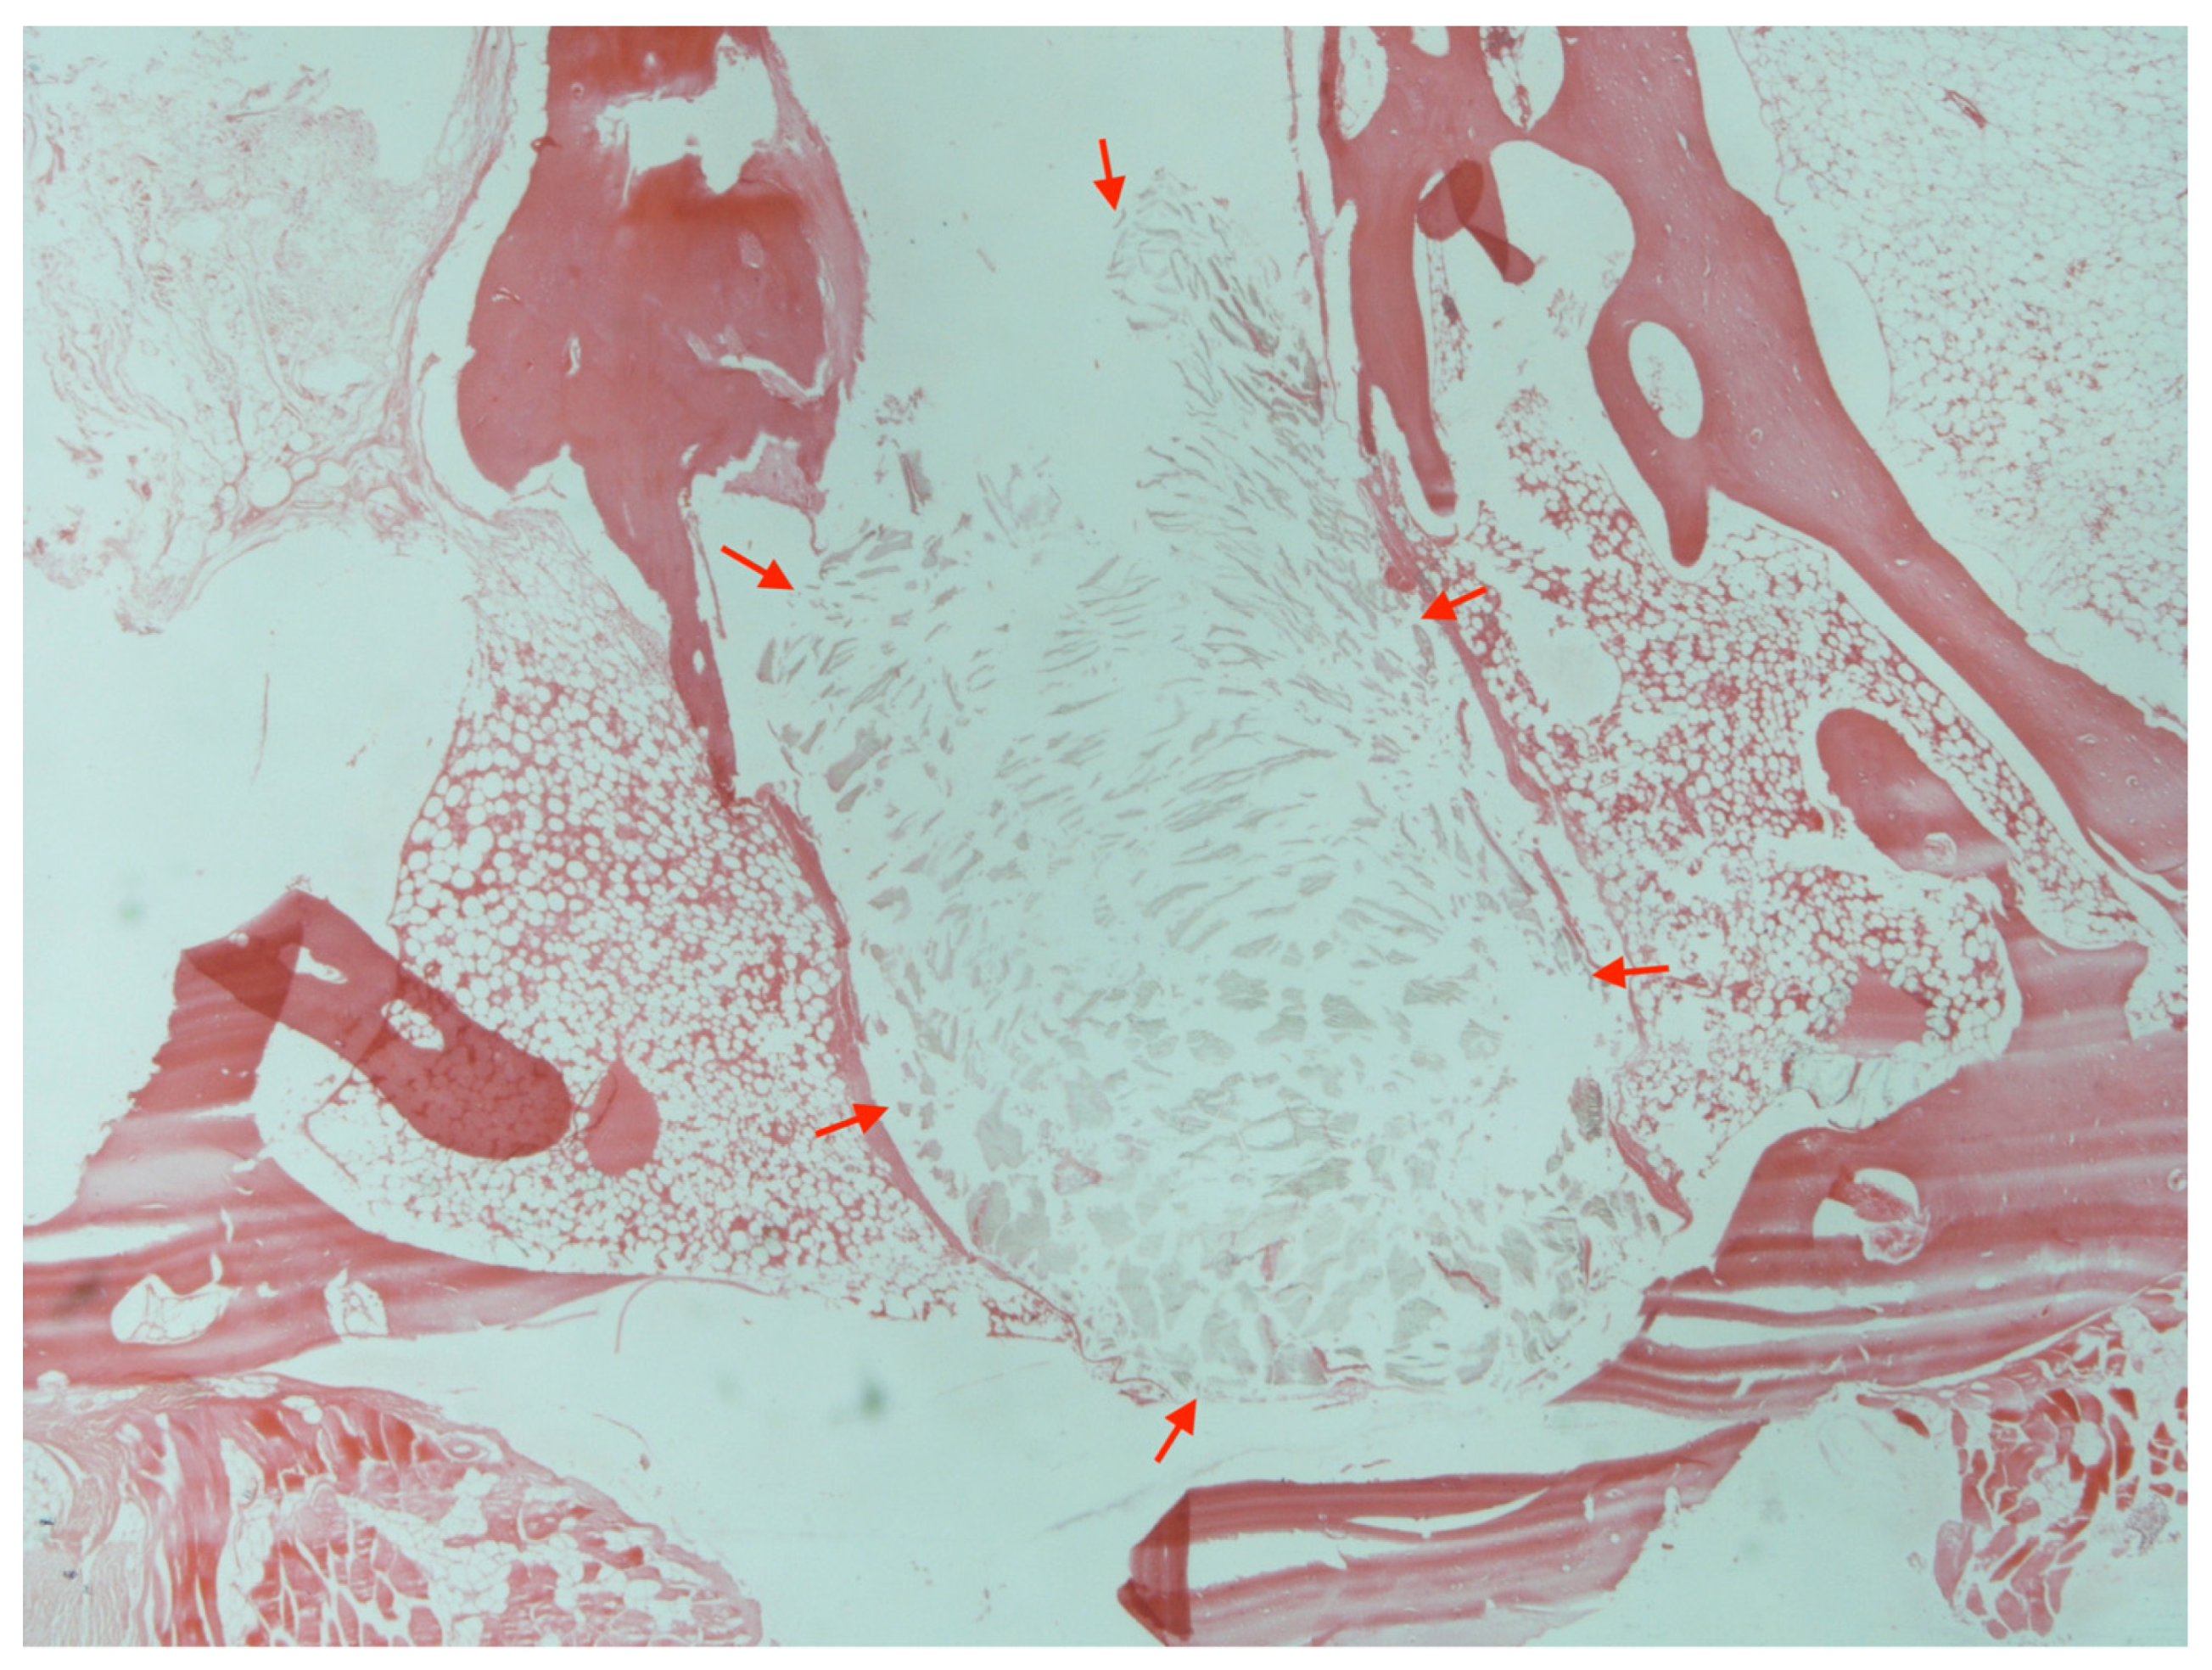

3.5. Histology

Histologic examination of samples from animals without any wound reaction did not reveal any bone or soft tissue abnormality (Figure 5). On the contrary, and in case of infection, loss of normal bone architecture, cortical thickening, and endocortical fibrosis were evident (Figure 6). When foreign-body reaction was apparent, numerous polymeric particles birefringent under polarized light were surrounded by macrophages and giant cells. Disruption of normal architecture with cortical thickening and dysplastic bone marrow were also observed (Figure 7).

Figure 7.

Histological image with particles of absorbable debris into the bone (red arrows) and loss of normal bone architecture in an animal with foreign-body reaction (H + E stain, ×200).